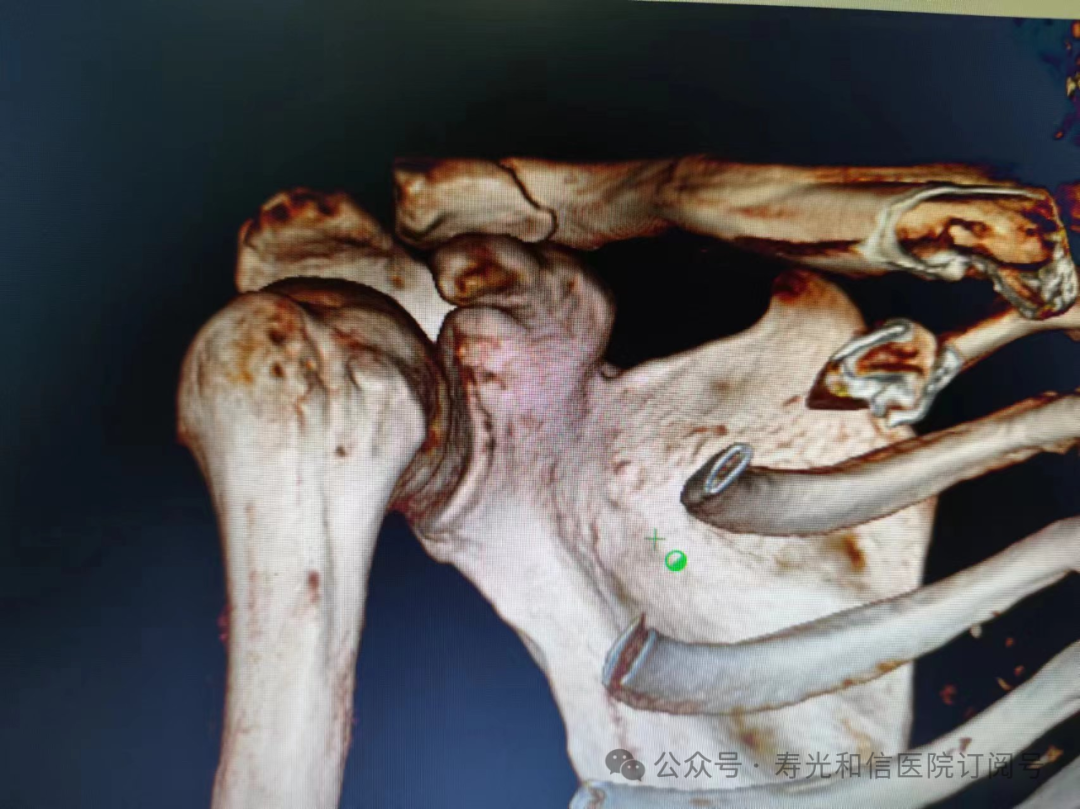

患者经120接诊,完善相关辅助检查后收入寿光和信医院骨外科。检查发现,患者右锁骨骨折、左股骨颈骨折、左大转子撕脱骨折、右膝关节前交叉韧带止点撕脱骨折、右膝关节外侧副韧带损伤、颅骨骨折及全身多处皮肤挫伤。因患者是外地来寿人员,家属短时间内不能赶过来,并且患者家庭经济条件较差,没有缴纳住院手术费的能力。但是股骨颈骨折后,股骨头坏死发生几率较高,手术越早进行,越有利于减少发生股骨头坏死的几率。骨外科主任李刚始终牢记救死扶伤的神圣职责,本着为病人负责的原则,坚定地选择先行为患者实行手术治疗。

与患者本人充分沟通后,李刚主任率领骨外科团队,经过充分的术前讨论及术前准备,于2024年9月1日为患者在全身麻醉下实施了4个半小时的内固定手术治疗。“时间就是生命”,手术过程中,全体参与人员密切观察病情变化,敏锐发现早期异常指标,争分夺秒,一丝不苟地做好各项抢救救治工作,做到瞬间判断、正确评估、果断处理,赢得了抢救患者的“黄金时机”,确保了手术的顺利完成。

在为其进行股骨颈骨折治疗时,手术团队为其采取了股骨颈动力交叉钉系统,这是一种新型股骨颈内固定系统,属微创植入,较从前的技术具有手术时间短、创伤小、力学稳定、滑动加压等优点。同时,患者恢复快,可早期离床、不负重下活动,缩短住院时间及康复时间,有效降低患者股骨颈骨折不愈合发生率,降低长期卧床合并症和死亡率。